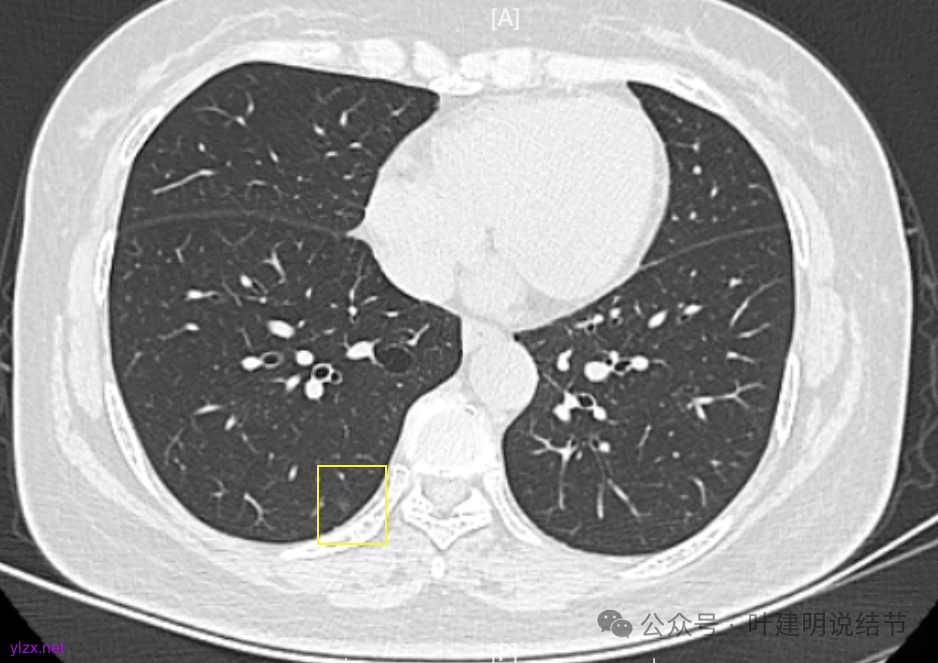

两肺多发结节,持续存在,总体上看,瘤肺边界清,轮廓清楚,主病灶有血管穿行,表面也不平,考虑微浸润性腺癌可能性大,其他2处不典型增生或原位癌可能性大些。总的来说,风险还不大,也不会引起胸痛症状,但因两侧都有,且可能后续均是要手术的,个人觉得左侧病灶可以考虑先切除,因为两个病灶离得不远,总的来说还是靠边缘的,定位后楔形切除能将两处都切了。这样只需再关注右侧的,以后真右侧也要手术,也可拉长两次手术的间隔时间,有利于恢复以及耐受性会好些。两侧同时手术,疼痛、咳嗽、恢复情况容易差些,也容易合并肺炎或其他并发症,安全性差一点的。以上意见供参考!

两肺多发磨玻璃结节,主病灶混合密度且有小血管进入,表面不平有毛刺,考虑微浸润性腺癌或浸润性腺癌可能性大,其余部分考虑原位癌或微浸润性腺癌,部分考虑肺泡上皮增生或不典型增生可能。总体上对比2022年说不上太明显的进展。但对于是否手术来讲,我仍倾向当年的意见,左侧的可以考虑近期亚肺叶(个人倾向楔切)切除,右侧的先随访,以后有进展并风险增加再考虑干预处理。因为要拉长两次手术的间隔,这样对机体的创伤与恢复更加有利一些。若定要仍不开刀,则建议要4-6个月复查,不过个人不太主张过于保守随访,对于像主病灶这种有少许实性成分的,不能保证肯定安全。意见供参考!